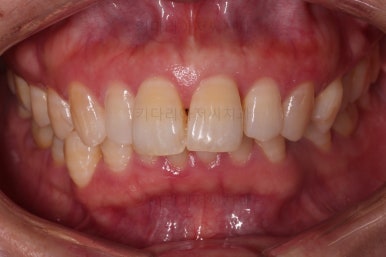

초진 시, 입안의 모습이에요.

"최근 들어 점점 틀어지고, 점점 튀어나오고, 점점 사이가 벌어져요."

성장이 끝난 성인들은 해가 갈수록 특히 아래앞니가 삐뚤어지는 것은 자연스러운데요.

이번 환자분의 말씀대로 최근에 변하가 심하게 나타난 경우는 원인이 딱 하나에요.

잇몸(치주)

흔히 풍치라고 하죠.

전반적인 잇몸이 나빠진다 -> 어금니가 씹는 힘에 버텨주지 못하고 앞으로 쓰러진다. -> 앞니가 강하게 부딪히며 아래앞니가 윗니를 앞으로 쳐낸다. -> 돌출입이 생기고, 앞니 사이 틈새가 생긴다.

앞니가 튀어나오고 틈새가 생기는 것이 결과이긴 하지만 원인은 어금니쪽 잇몸에서부터 찾아야해요.